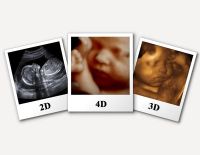

Siêu âm 3D là kĩ thuật siêu âm y khoa, sử dụng chủ yếu để chẩn đoán thai nhi, tim, hậu môn - trực tràng, mạch máu. Hiện nay, nhắc tới siêu âm, siêu âm 3D được người ta nói đến rất nhiều. Vậy nó...

Siêu âm 2D – Những thông tin mẹ bầu nên nắm bắt kịp thời

Siêu âm 2D là hình thức siêu âm dành cho các mẹ bầu ở những tuần đầu của thai kỳ. Đây là phương pháp siêu âm cũ nhưng vẫn được áp dụng nhiều hiện nay. Khi siêu âm 2D các mẹ bầu vẫn nắm được...